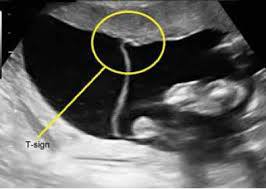

O “Sinal do T” na ultrassonografia é indicativo de qual tipo de gestação gemelar?

Monocoriônica.